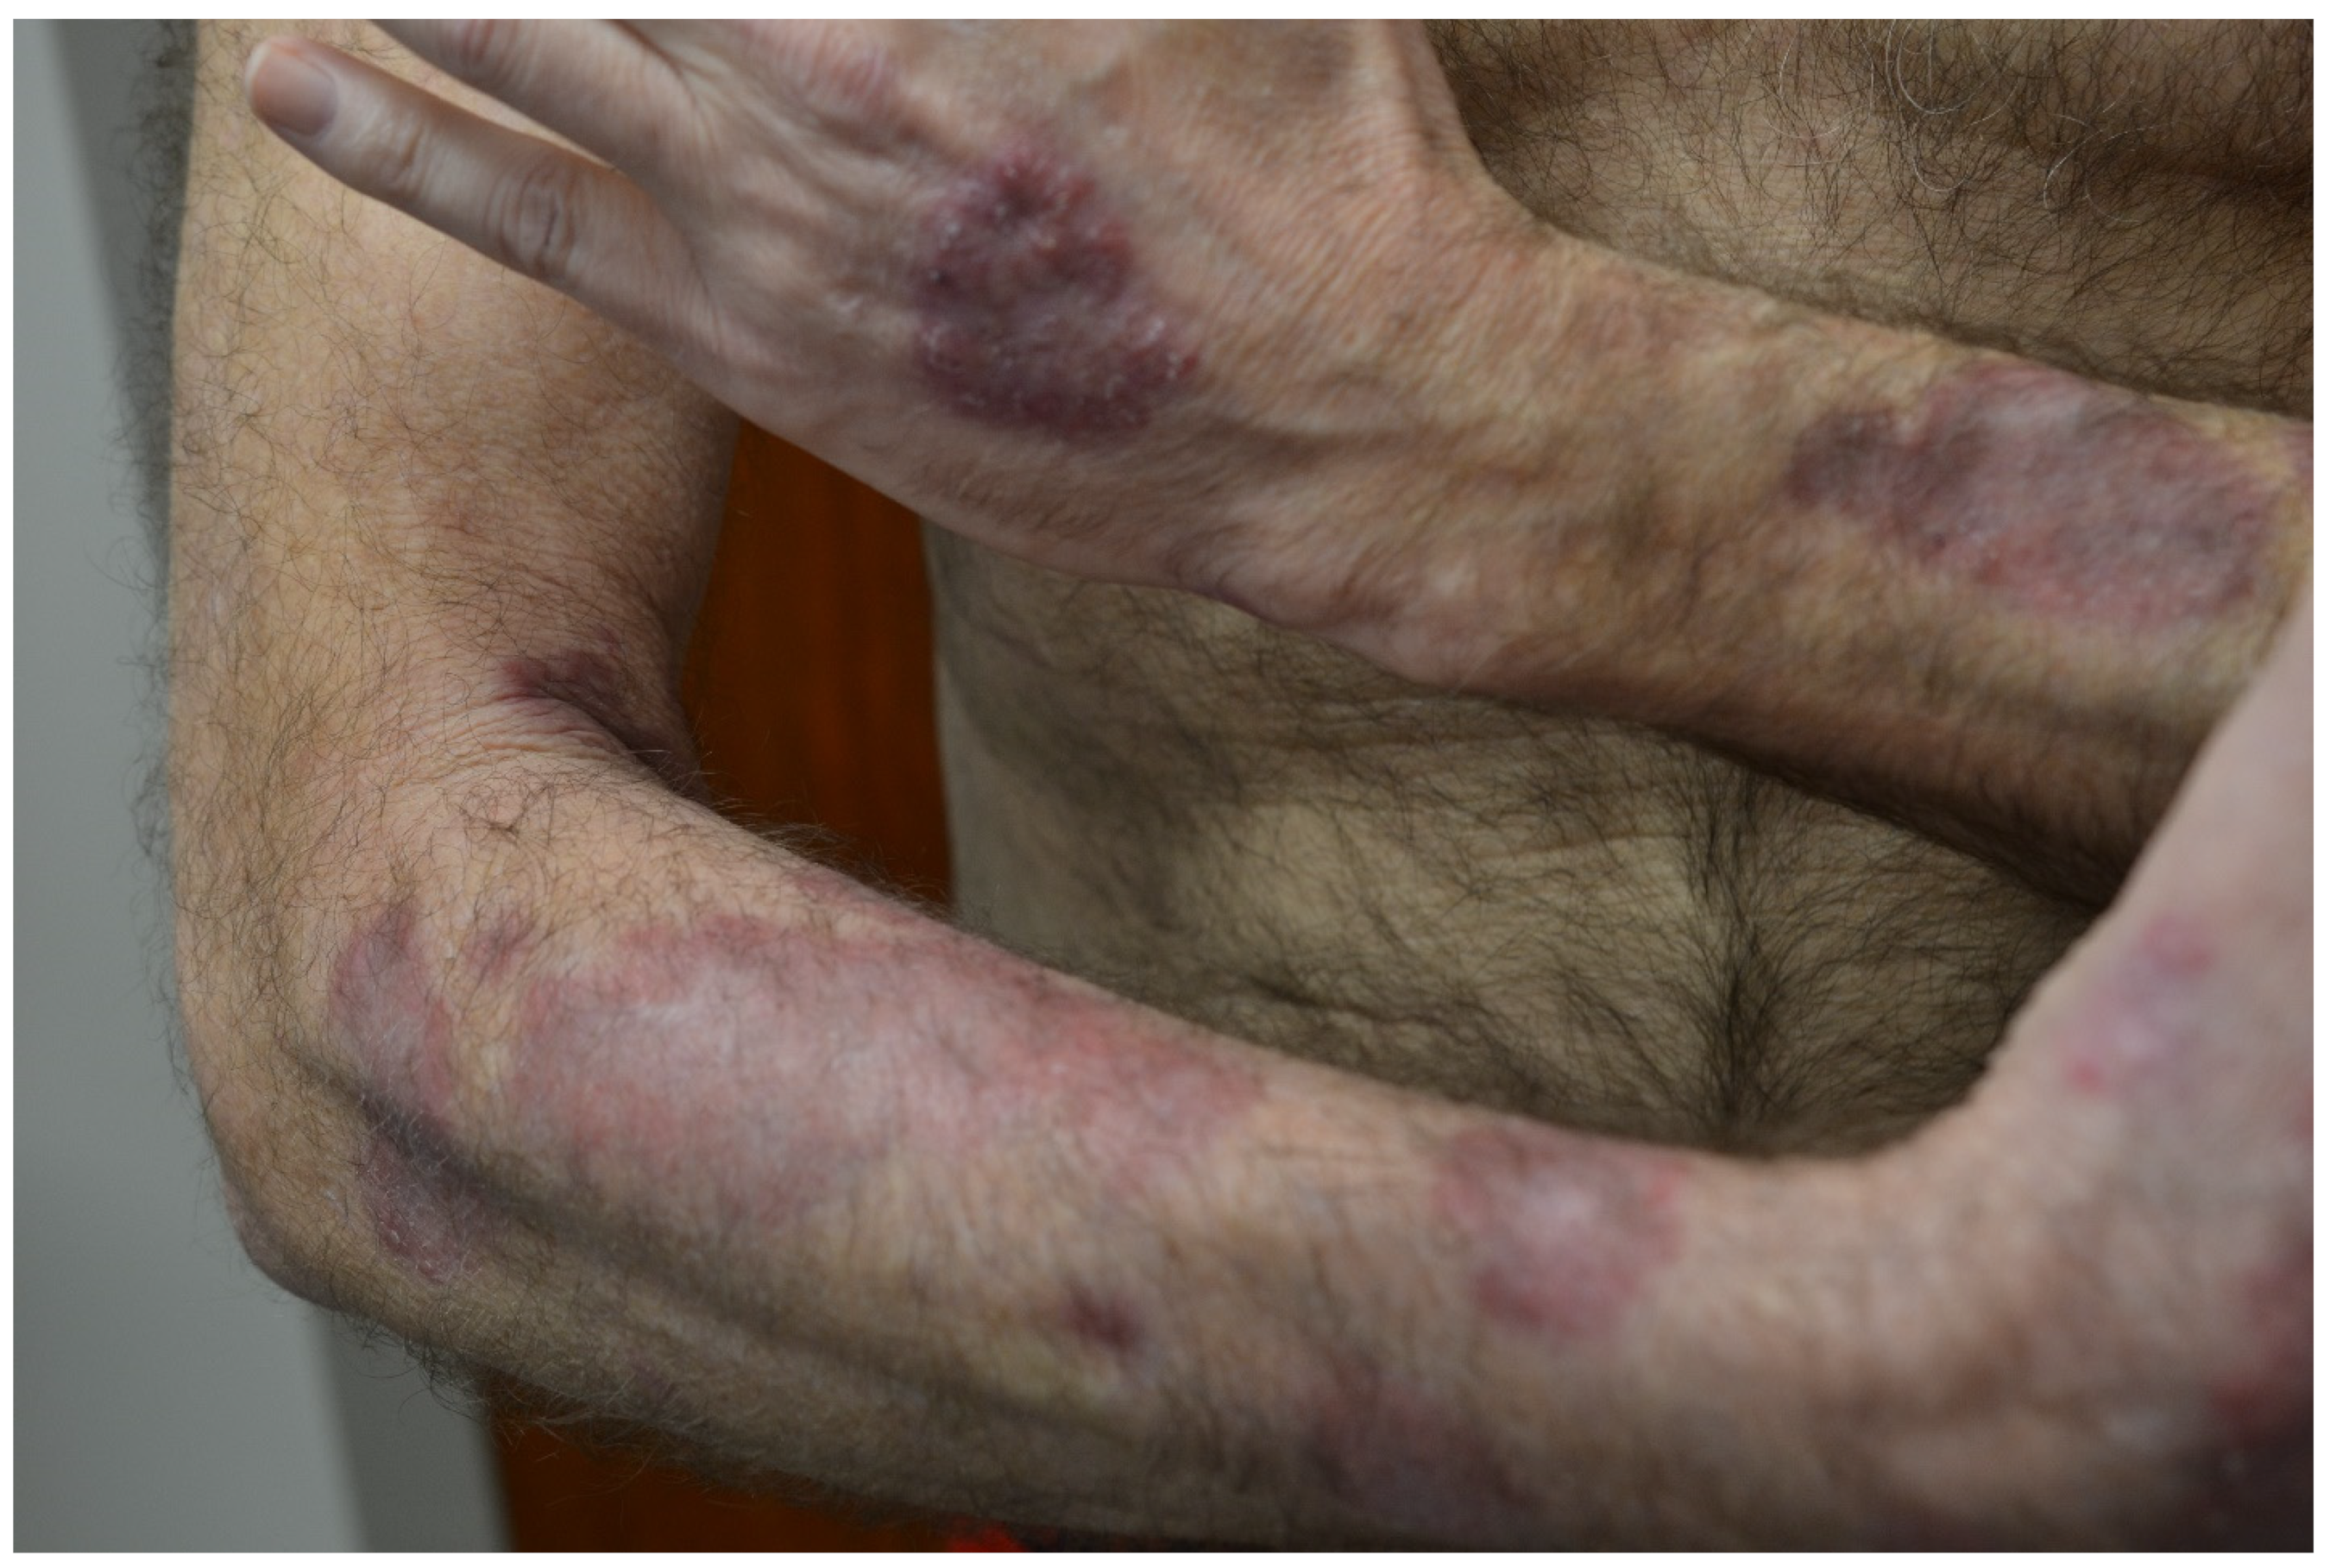

3.3.2. Rheumatoid Vasculitis

| Rheumatoid Vasculitis | Severe RA features, cutaneous vasculitis, medium-sized artery necrotizing vasculitis, vasculitic peripheral neuropathy, ocular disease, cardiac disease, low serum complement C3 | RA symptoms, deep leg ulcers, palpable purpura, rash, sores around nails, constitutional symptoms (fever, fatigue, weight loss), sensory neuropathy, visual disturbances | -Non-vasculitic RA cutaneous syndromes: Sweet syndrome, pyoderma gangrenosum -Other vasculitides: PAN, ANCA-associated, cryoglobulinemic, paraneoplastic -Vasculitis mimics: Infection, malignancy, endocarditis, thromboembolic diseases | -Corticosteroids and immunosuppressive therapy -Targeted immunotherapies: rituximab, infliximab, etanercept, tocilizumab, peficitinib |